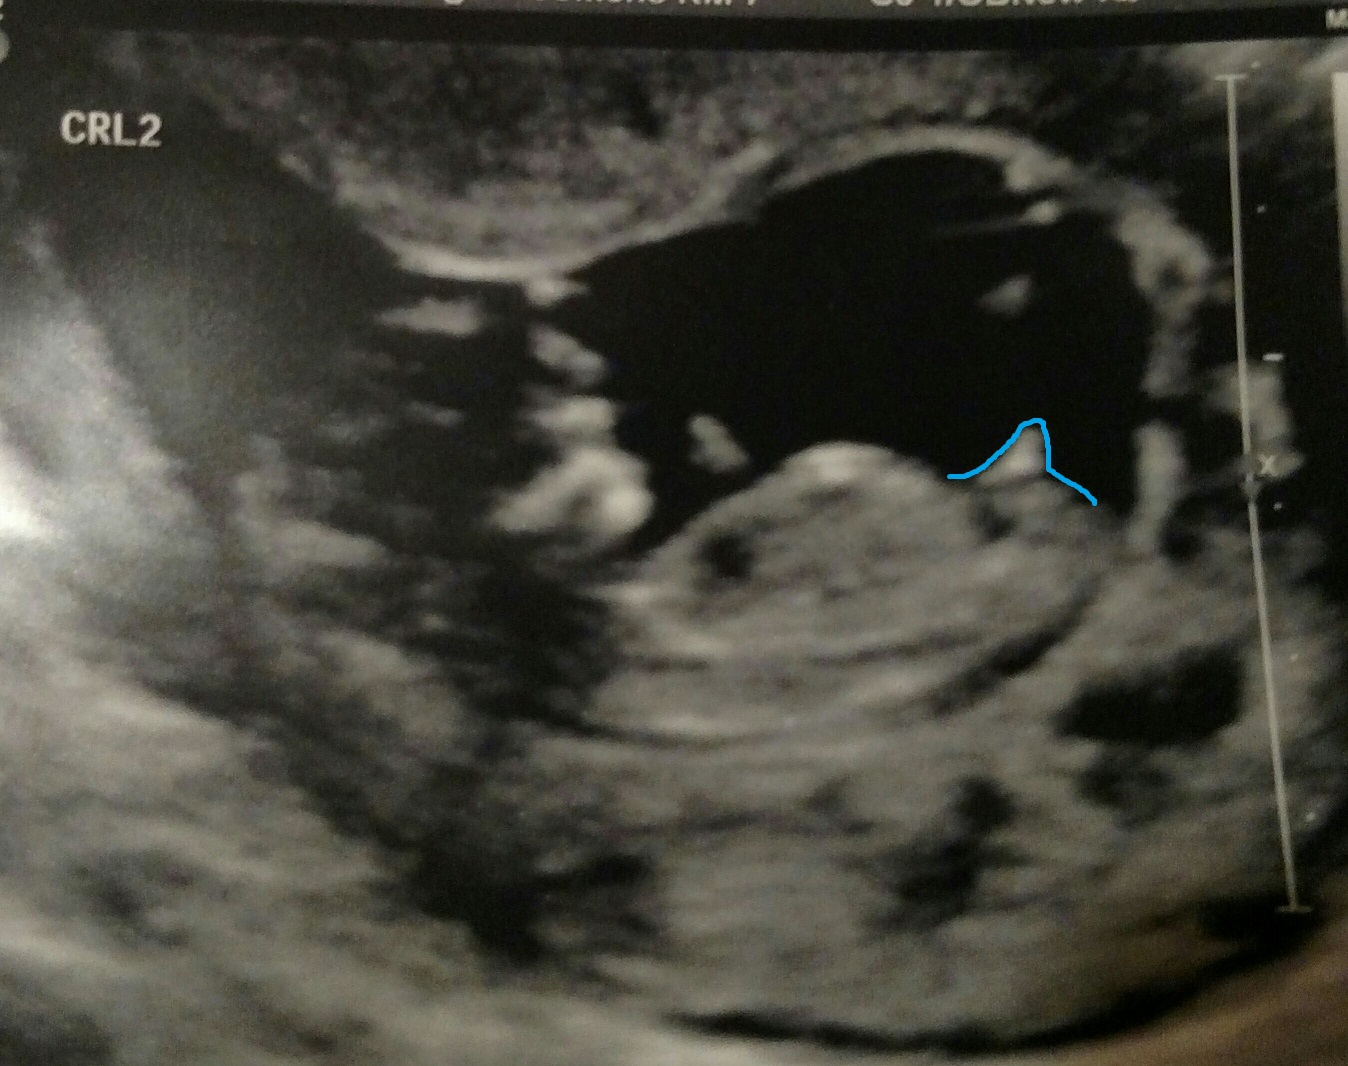

Hey everybody! We just had our 2 week appointment and got to see our little one again. I'm curious as to what you all think about the little one's nub... Boy or girl? Let me know what you think!